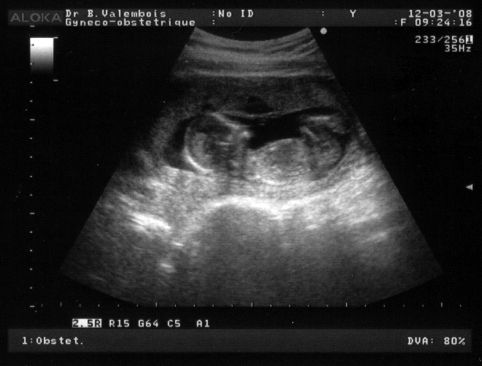

Dès que le gynéco a posé la sonde sur mon ventre, tu avais les jambes bien écartées et le zizi bien visible, aucun doute possible! Donc tu t'appelleras Elliott... C'est ça le bonheur!

Après, on a regardé ton profil, tu gigotes beaucoup mais le gynéco a réussi à prendre une superbe photo de toi...